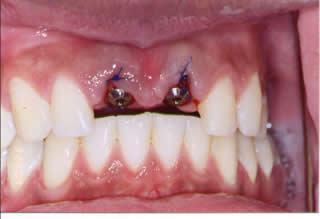

Immediate Implants:

Very commonly the two front teeth are lost due to accident.

Two immediate implants were placed at the same time the teeth were taken out and two temporary crowns were made.

Patient walked in with two fractured teeth and left the office with two dental implants and temporary crowns completed in the same time.